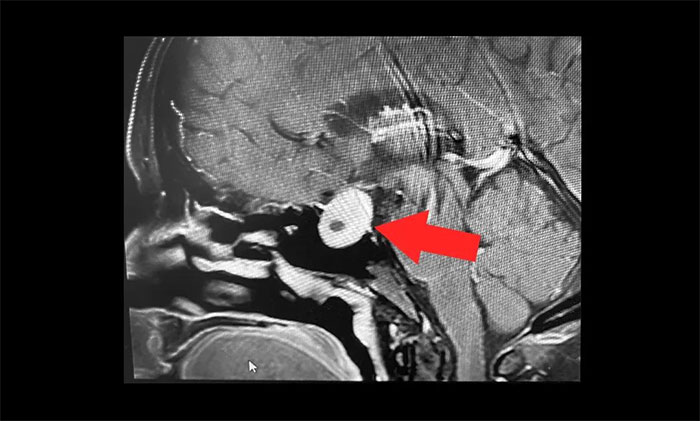

▲ 虽然无功能性垂体瘤并不具有内分泌功能,但由于瘤体较大,已经压迫视神经,丘脑垂体,如果不手术,任其发展将可能导致患者视力下降、视野缺损,甚至失明。

无功能性垂体瘤最常见的并发症是压迫视神经,临床上患者大多是五六十岁的中老年人,出现类似于老花眼、青光眼、白内障的症状。这种情况容易误诊、漏诊,患者到眼科做了一些对症治疗,症状却没有改善。李士其教授提醒,如果出现莫名的头痛、头晕或视力短期内急剧下降,应及时就医,行鞍区头颅磁共振检查。